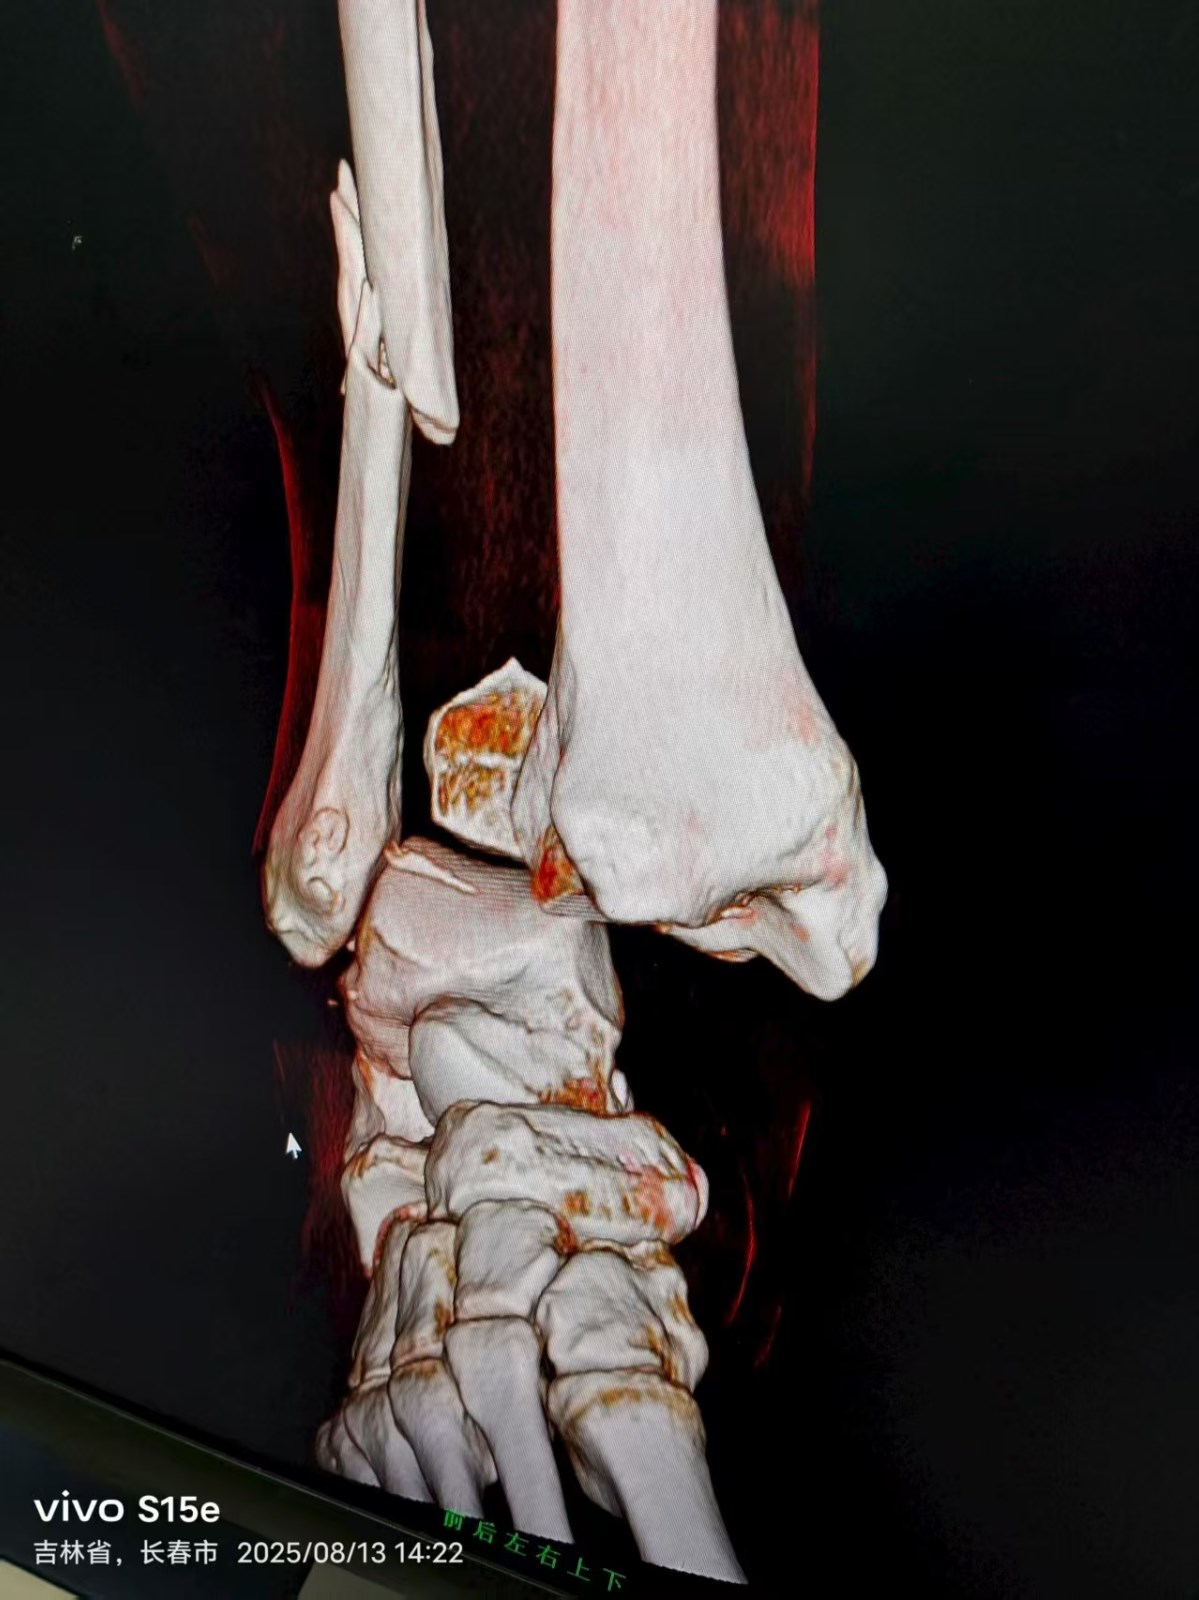

患者王某,骑电动车在上班途中,被迎面急驰而来的快递员电动车撞倒,导致右踝关节受伤,被我院120急救车接到医院,经摄片检查,确诊患者右踝关节骨折伴脱位,需要住院手术治疗。

8月14日上午,董庆武主任带领骨科团队,在全麻麻醉下,为患者行右外踝切开复位锁定钛板螺钉内固定,后踝切开复位拉力螺钉内固定,术中,专家团队凭借精湛医术和丰富经验,精准地对骨折部位进行复位和固定,术后摄片效果满意。